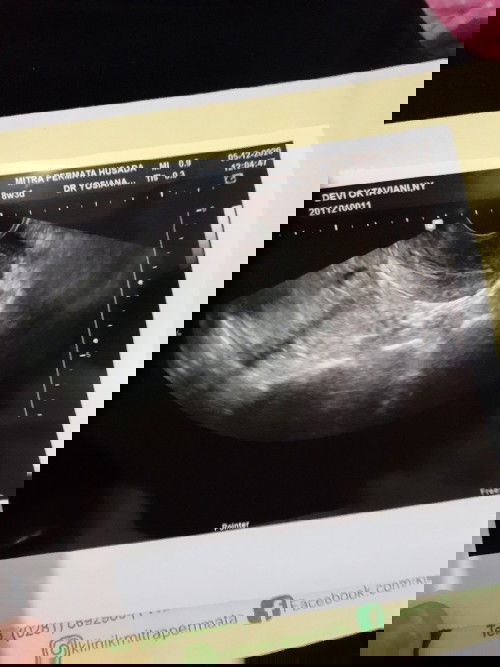

Alhamdulillah saya sdg hamil anak pertama UK 7w, cuma seminggu kemarin sempet keluar flek dan darah seperti haid. Takut banget kata dokter bisa ikut luruh kantung janinnya, diminta buat balik 2 mggu lagi. Saya jadi kepikiran terus sampe berkali kali tespek karena takut kenapa kenapa janinnya. Kadang jd mikir yg aneh aneh. Bunda semua apakah punya tips supaya tetap tenang dan mengurangi rasa cemas? Mohon doanya jg semoga janin dan ibunya sehat aamiin #pregnancy

Keluar Flek hingga seperti darah haid

Mohon doanya ya bunda semua... saya hamil 6 weeks tapi keluar flek. Saat periksa, alhamdulillah masih ada kantung janin kata dokter tapi ada perdarahan dan terancam keguguran sehingga harus bedrest total.. Awalnya sedikit dan berwarna coklat, tapi lama lama netes seperti darah haid dan ada darah beku sedikit yg keluar. Saya takut banget sampai berpikir yang aneh aneh, sempet pinsan juga kemarin. Tp pagi tadi saya tespek alhamdulillah masih 2 garis. Mohon doanya ya bun semoga janin saya sehat, kuat dan bisa berkembang dengan baik. Semoga perdarahannya juga bisa berhenti karena sampai skrg masih keluar :") #firstbaby #pregnancy #mohondoanya